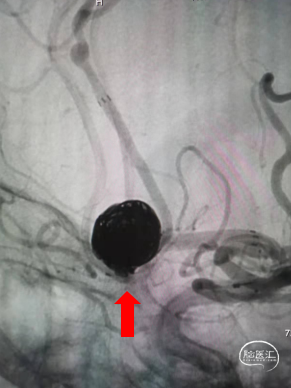

DSA结果:造影发现前交通动脉瘤,3D成像测量直径12mm,载瘤动脉直径1.85mm

术前3D-DSA造影:测量动脉瘤直径在12mm,载瘤动脉直径1.85mm。

第一个圈首先选用12mm*40cm弹簧圈顺利成篮。此时,部分弹簧圈突入同侧A2段。